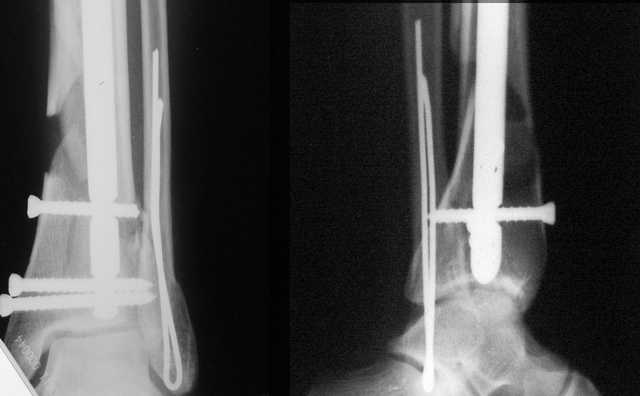

Классически показанием для locked nail яв-ся зоны BC CD, до появления LCP показания к locked nail несколько расширялись в зоны AB и DE

Аргументы: перелом достаточно низкий, трудно будет ввести 3-и блок. винта, а учитывая характер перелома на 2-х дистальных винтах я бы не рекомендовал немедленную полную нагрузку.

АМ> Аргументы: перелом достаточно низкий, трудно будет ввести 3-и блок.

АМ> винта, а учитывая характер перелома на 2-х дистальных винтах я бы не

АМ> рекомендовал немедленную полную нагрузку.

Положим, и с 2 винтами она к 2 месяцам была бы тут вполне реальна. Кроме того, есть возможность ввести винты мимо гвоздя (Poller), и таки разрешить раннюю полную нагрузку (что еще зависит от массы тела пациента и диаметра винтов). А уж если сопоставить стоимость отечественного гвоздика и пластины Synthes... Если бы на порядок более дорогая железка давала на тот же порядок лучший результат... ;-)